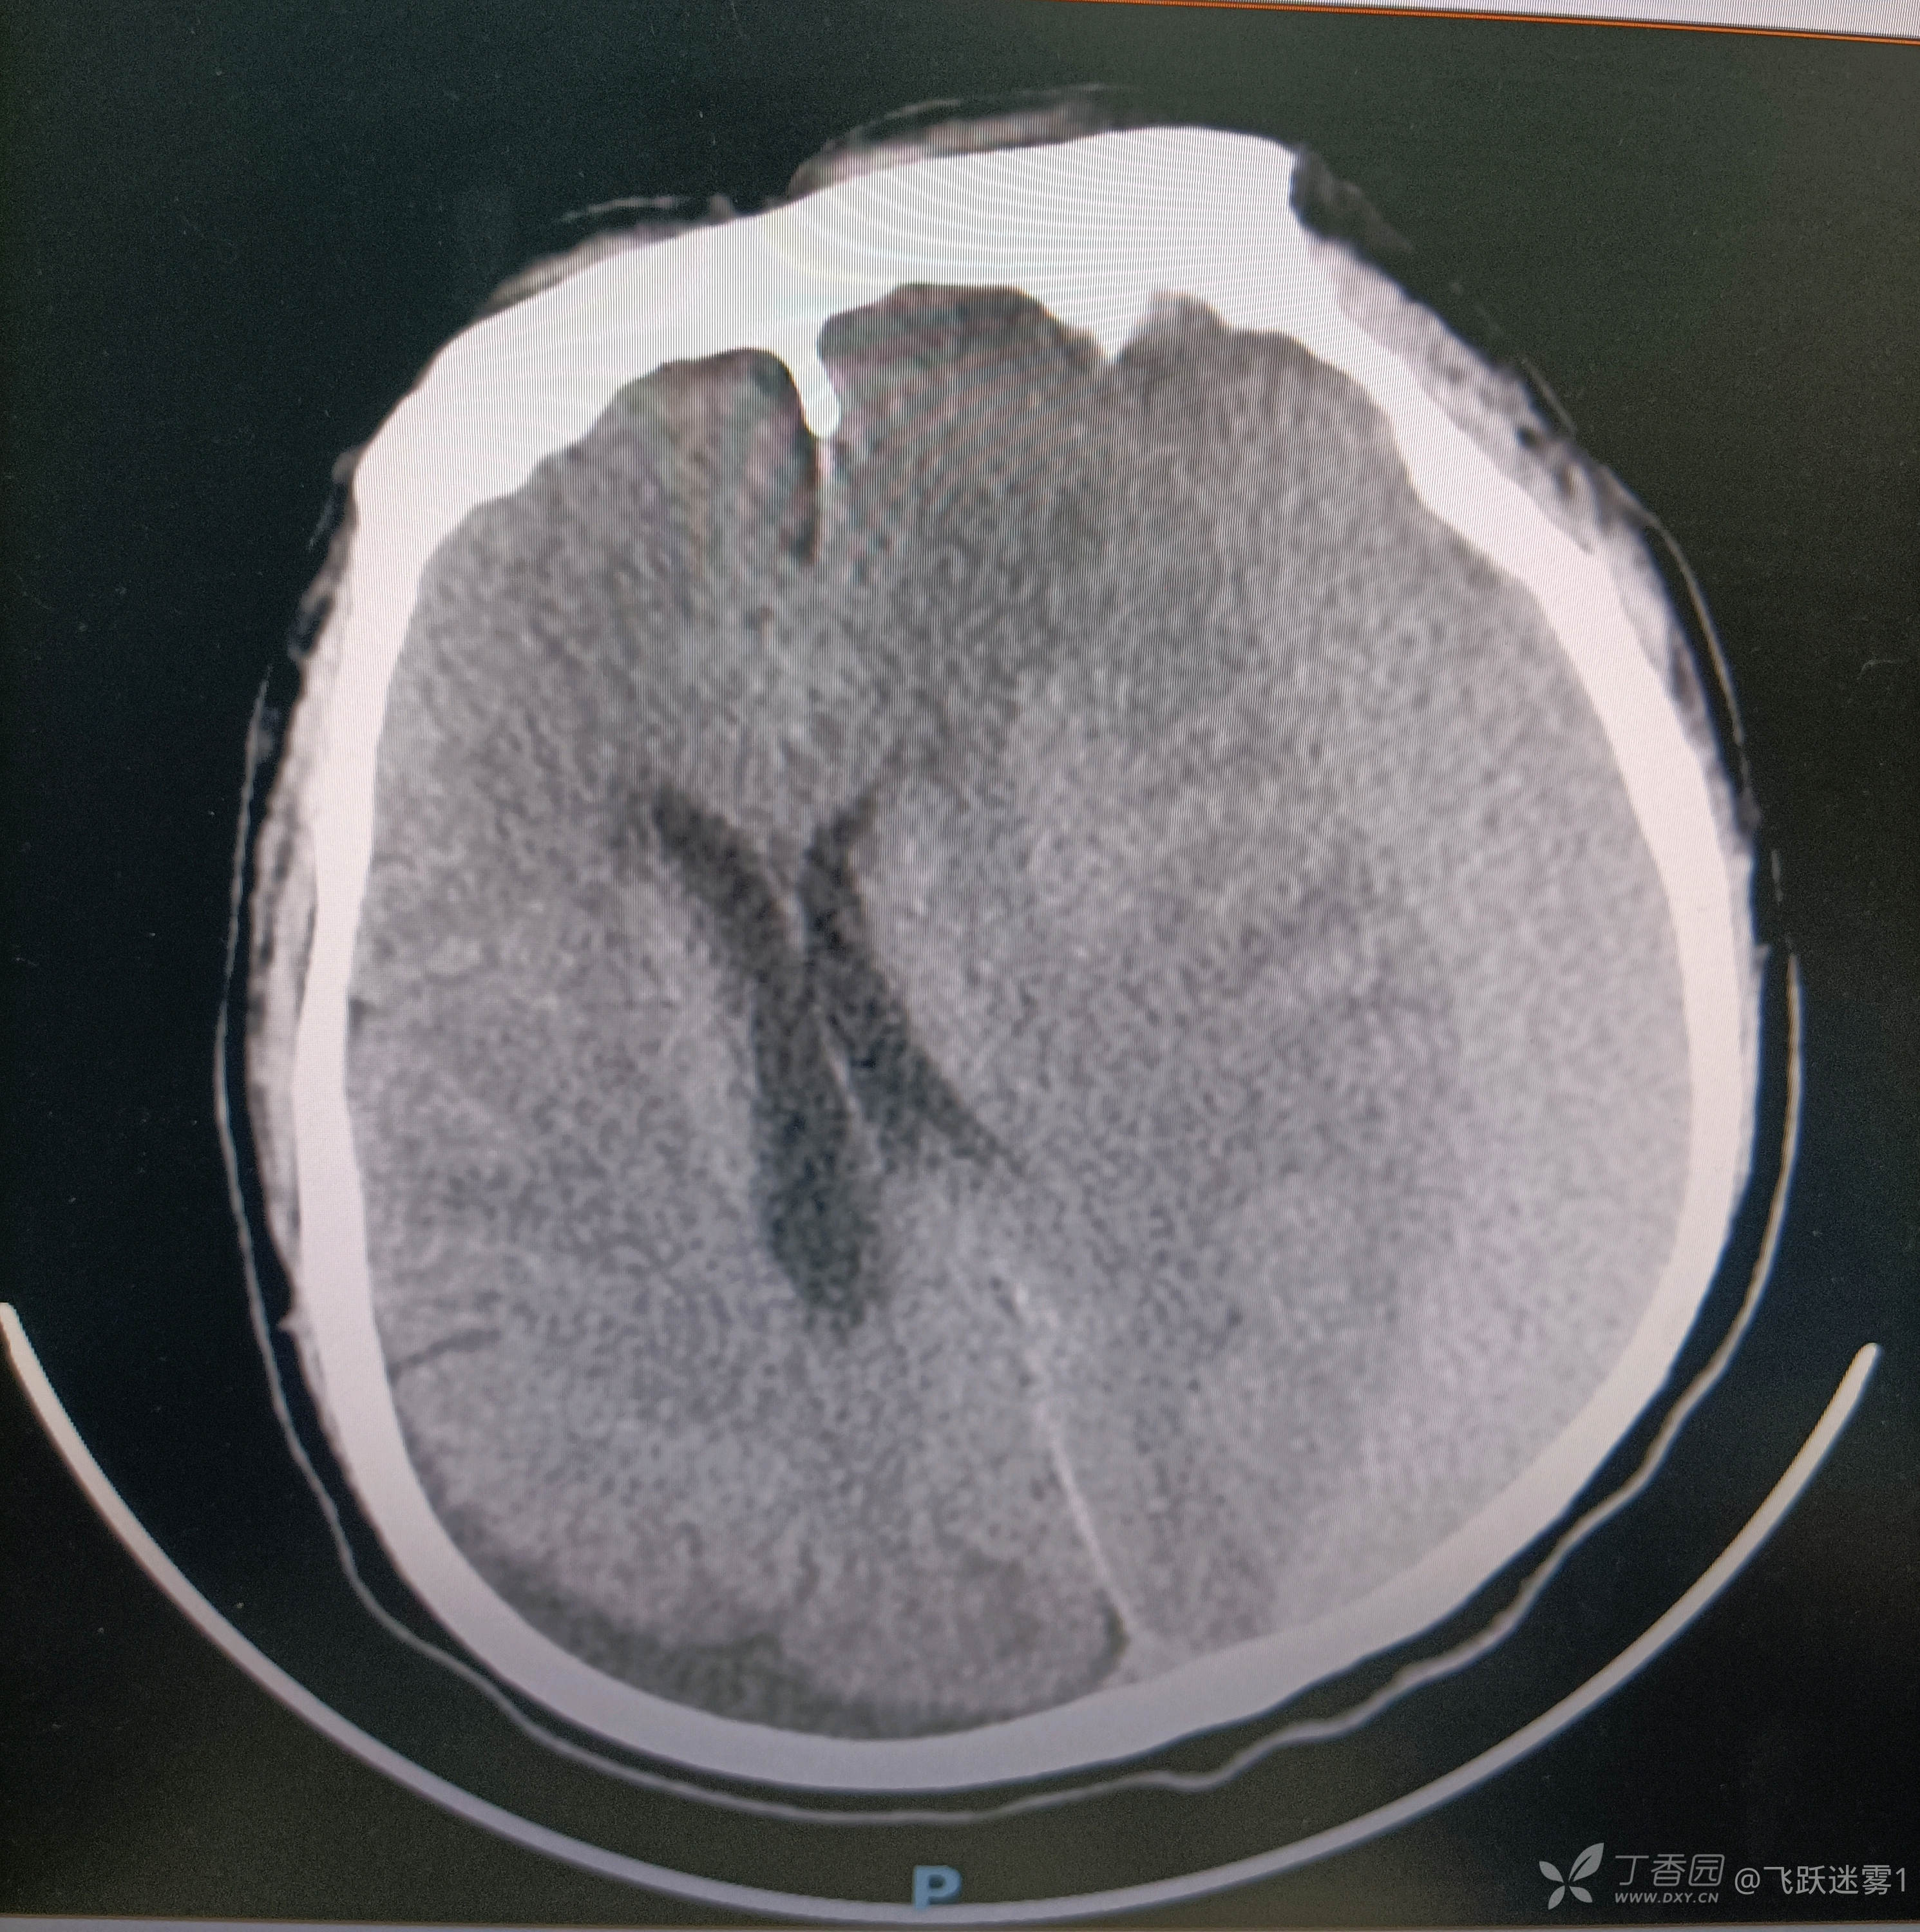

下一步颅脑CT,惊天大血肿

诊断:慢性硬膜下血肿